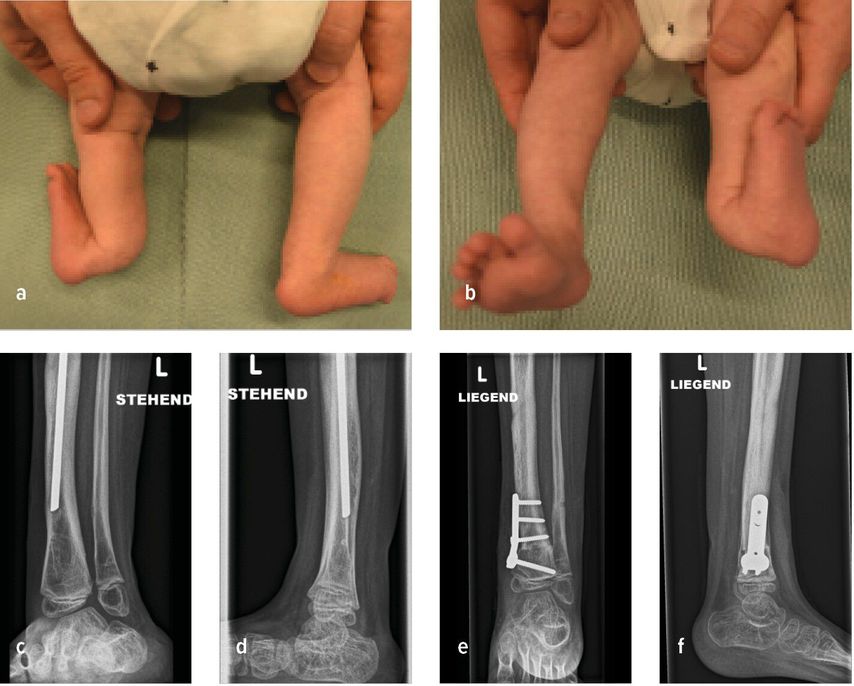

Abb. 1: 6-Jähriger mit unilateraler FH und 4-strahligem Fuß rechts sowie ausgeprägter Beinlängendifferenz vor chirurgischer Rekonstruktion (a–c). Laufende Valguskorrektur und Beinlängenausgleich mittels externen hexapoden Fixateurs mit Fußeinschluss

Die neuere Unterteilung nach Paley bezieht die Sprunggelenkspathologien in die Klassifikation mit ein (vier Typen mit Untergruppen) und gibt auch hier Empfehlung zu operativen Verfahren ab.1 Ziele der chirurgischen Rekonstruktion umfassen die Fußkorrektur mit plantigrader Position, den Ausgleich der Beinlängendifferenz bei Wachstumsabschluss sowie eine neutrale Beinachse. Neben konservativen Maßnahmen wie Schuhzurichtungen und Orthosenversorgung, erfolgt die Korrektur schließlich über chirurgische Verfahren wie Stabilisierungstechniken des Knie- und Sprunggelenkes, Wachstumslenkung sowie beinverlängernde Maßnahmen. Im Fall des 6-jährigen Patienten erfolgten eine Valguskorrektur und ein Beinlängenausgleich mittels externen hexapoden Fixateurs und Fußeinschluss (Abb.1d,e).6 In besonders schweren Fällen mit ausgeprägter Fehlbildung und Hypoplasie des Fußes kann eine Amputation mit anschließender Orthoprothesenversorgung in Betracht gezogen werden.7